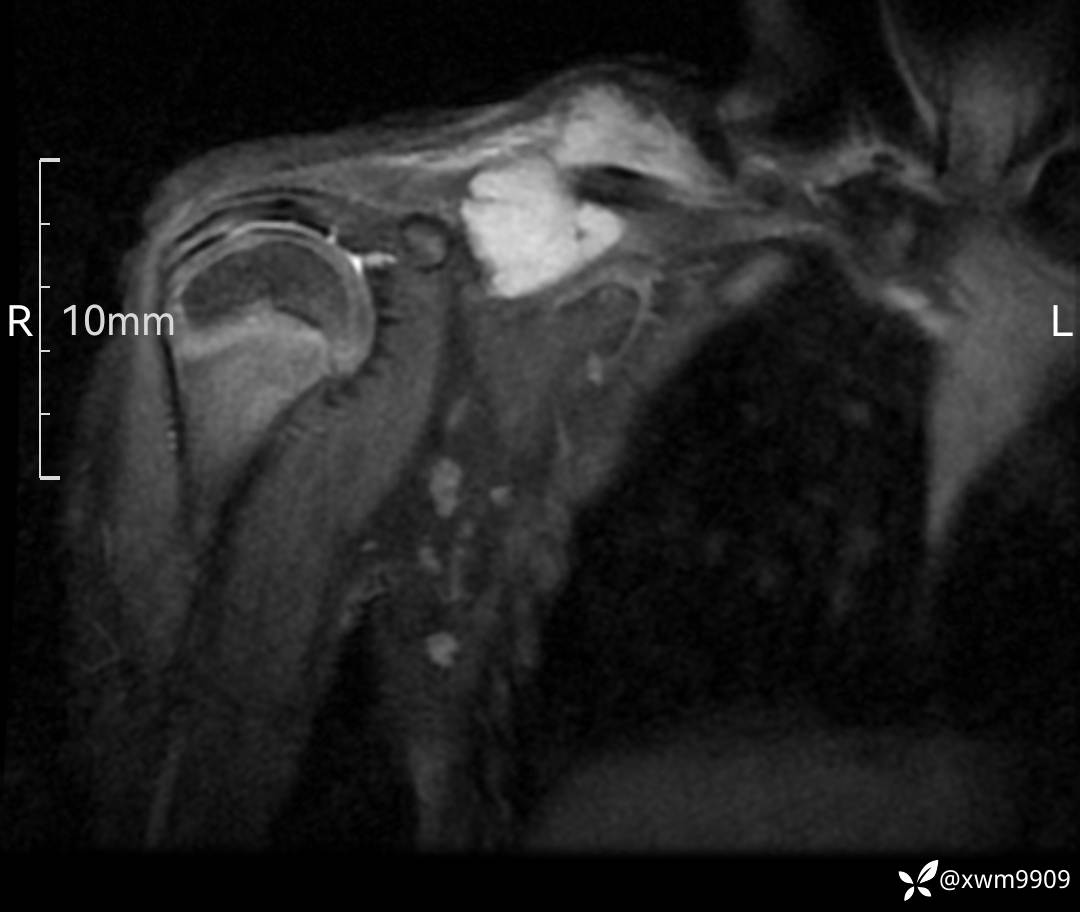

3、查体,右锁下方可及一约5x6Cm肿物,软丶边清丶未见明显发红,肤温不高,压痛明显,不可推动,稍有波动感。其他无特殊。

CT:

2、CT、MR肿块内可见液-液平面,常见有哪些疾病。